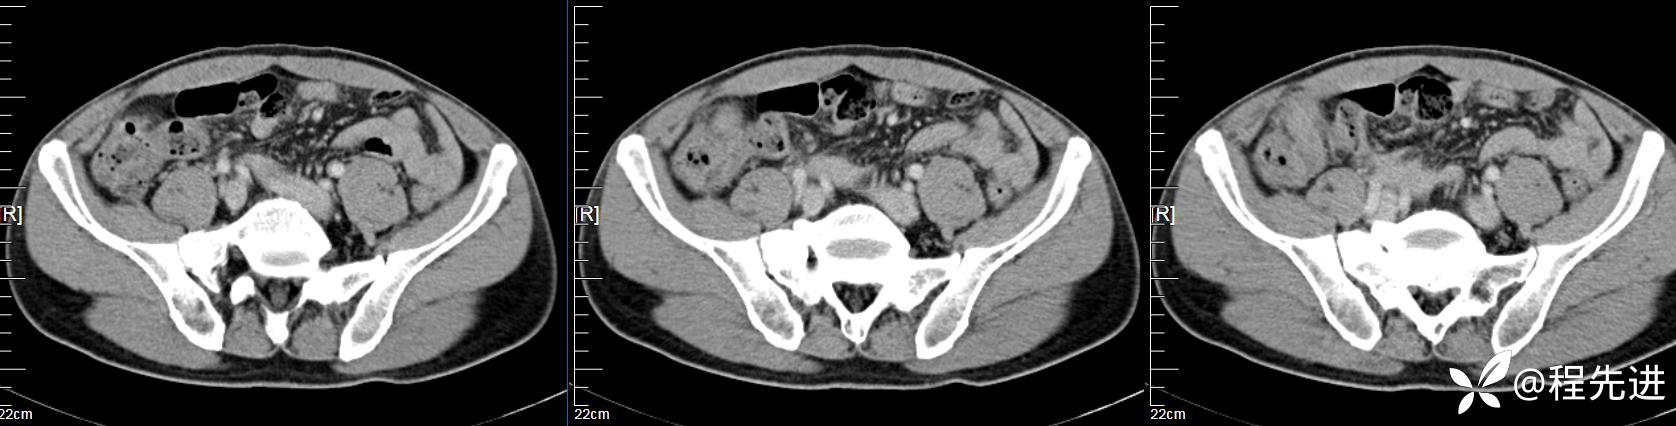

【患者信息】:男,61岁

【现病史及既往史】:右下腹部疼痛伴腹胀2天

【影像检查】